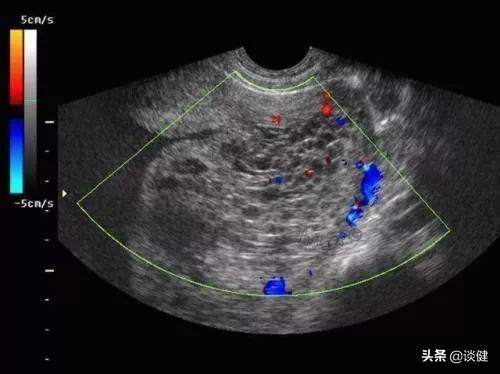

●流产:因为流产是在怀孕的前12周中最常见的情况,所以它往往是孕早期出血最令人担忧的问题之一。但是,早孕期的出血并不一定意味着我们失去胎儿。实际上,如果在彩超下观察到胎儿原始血管搏动,则超过90%的孕妇是不会失去胎儿的。一般而言,流产的症状是强烈的下腹部痉挛、腹痛、阴道出血量也比较多,持续的时间相对较长。

●异位妊娠 :异位妊娠也被称之为宫外孕。在异位妊娠中,受精的胚胎在输卵管内植入子宫外。如果胚胎持续生长,可能会导致输卵管破裂,从而危及孕妇的生命。尽管异位妊娠有潜在危险,但它在孕妇中发生率仅为2%。异位妊娠大约6~8周出现阴道流血,还可能出现下腹部强烈痉挛或疼痛,以及头昏眼花,严重者会大量出血危及生命安全。